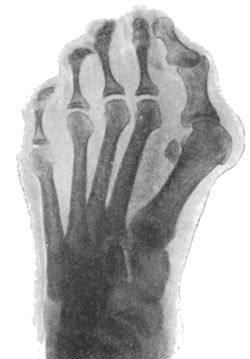

| 157. | Radiogram of Hallux Valgus | 296 |

| 158. | Radiogram of Hallux Varus or Pigeon-Toe | 298 |